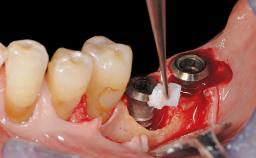

Mauricio Araujo and Flauvia Matarazzo present this straightforward clinical case, demonstrating the potential effect of implant placement depth on the resolution of peri-implant treatment. A 42-year-old systemically healthy female patient, a non-smoker with no history of periodontitis, was treated at the Dental Clinic at the State University of Maringá, Brazil between 2008 and 2009, when she received five implants restored with single crowns at sites 14, 26, 27, 36, and 46. After delivery of the implant-supported prosthetic restorations, the patient was enrolled in the supportive peri-implant therapy (SPiT) maintenance program at the same university.